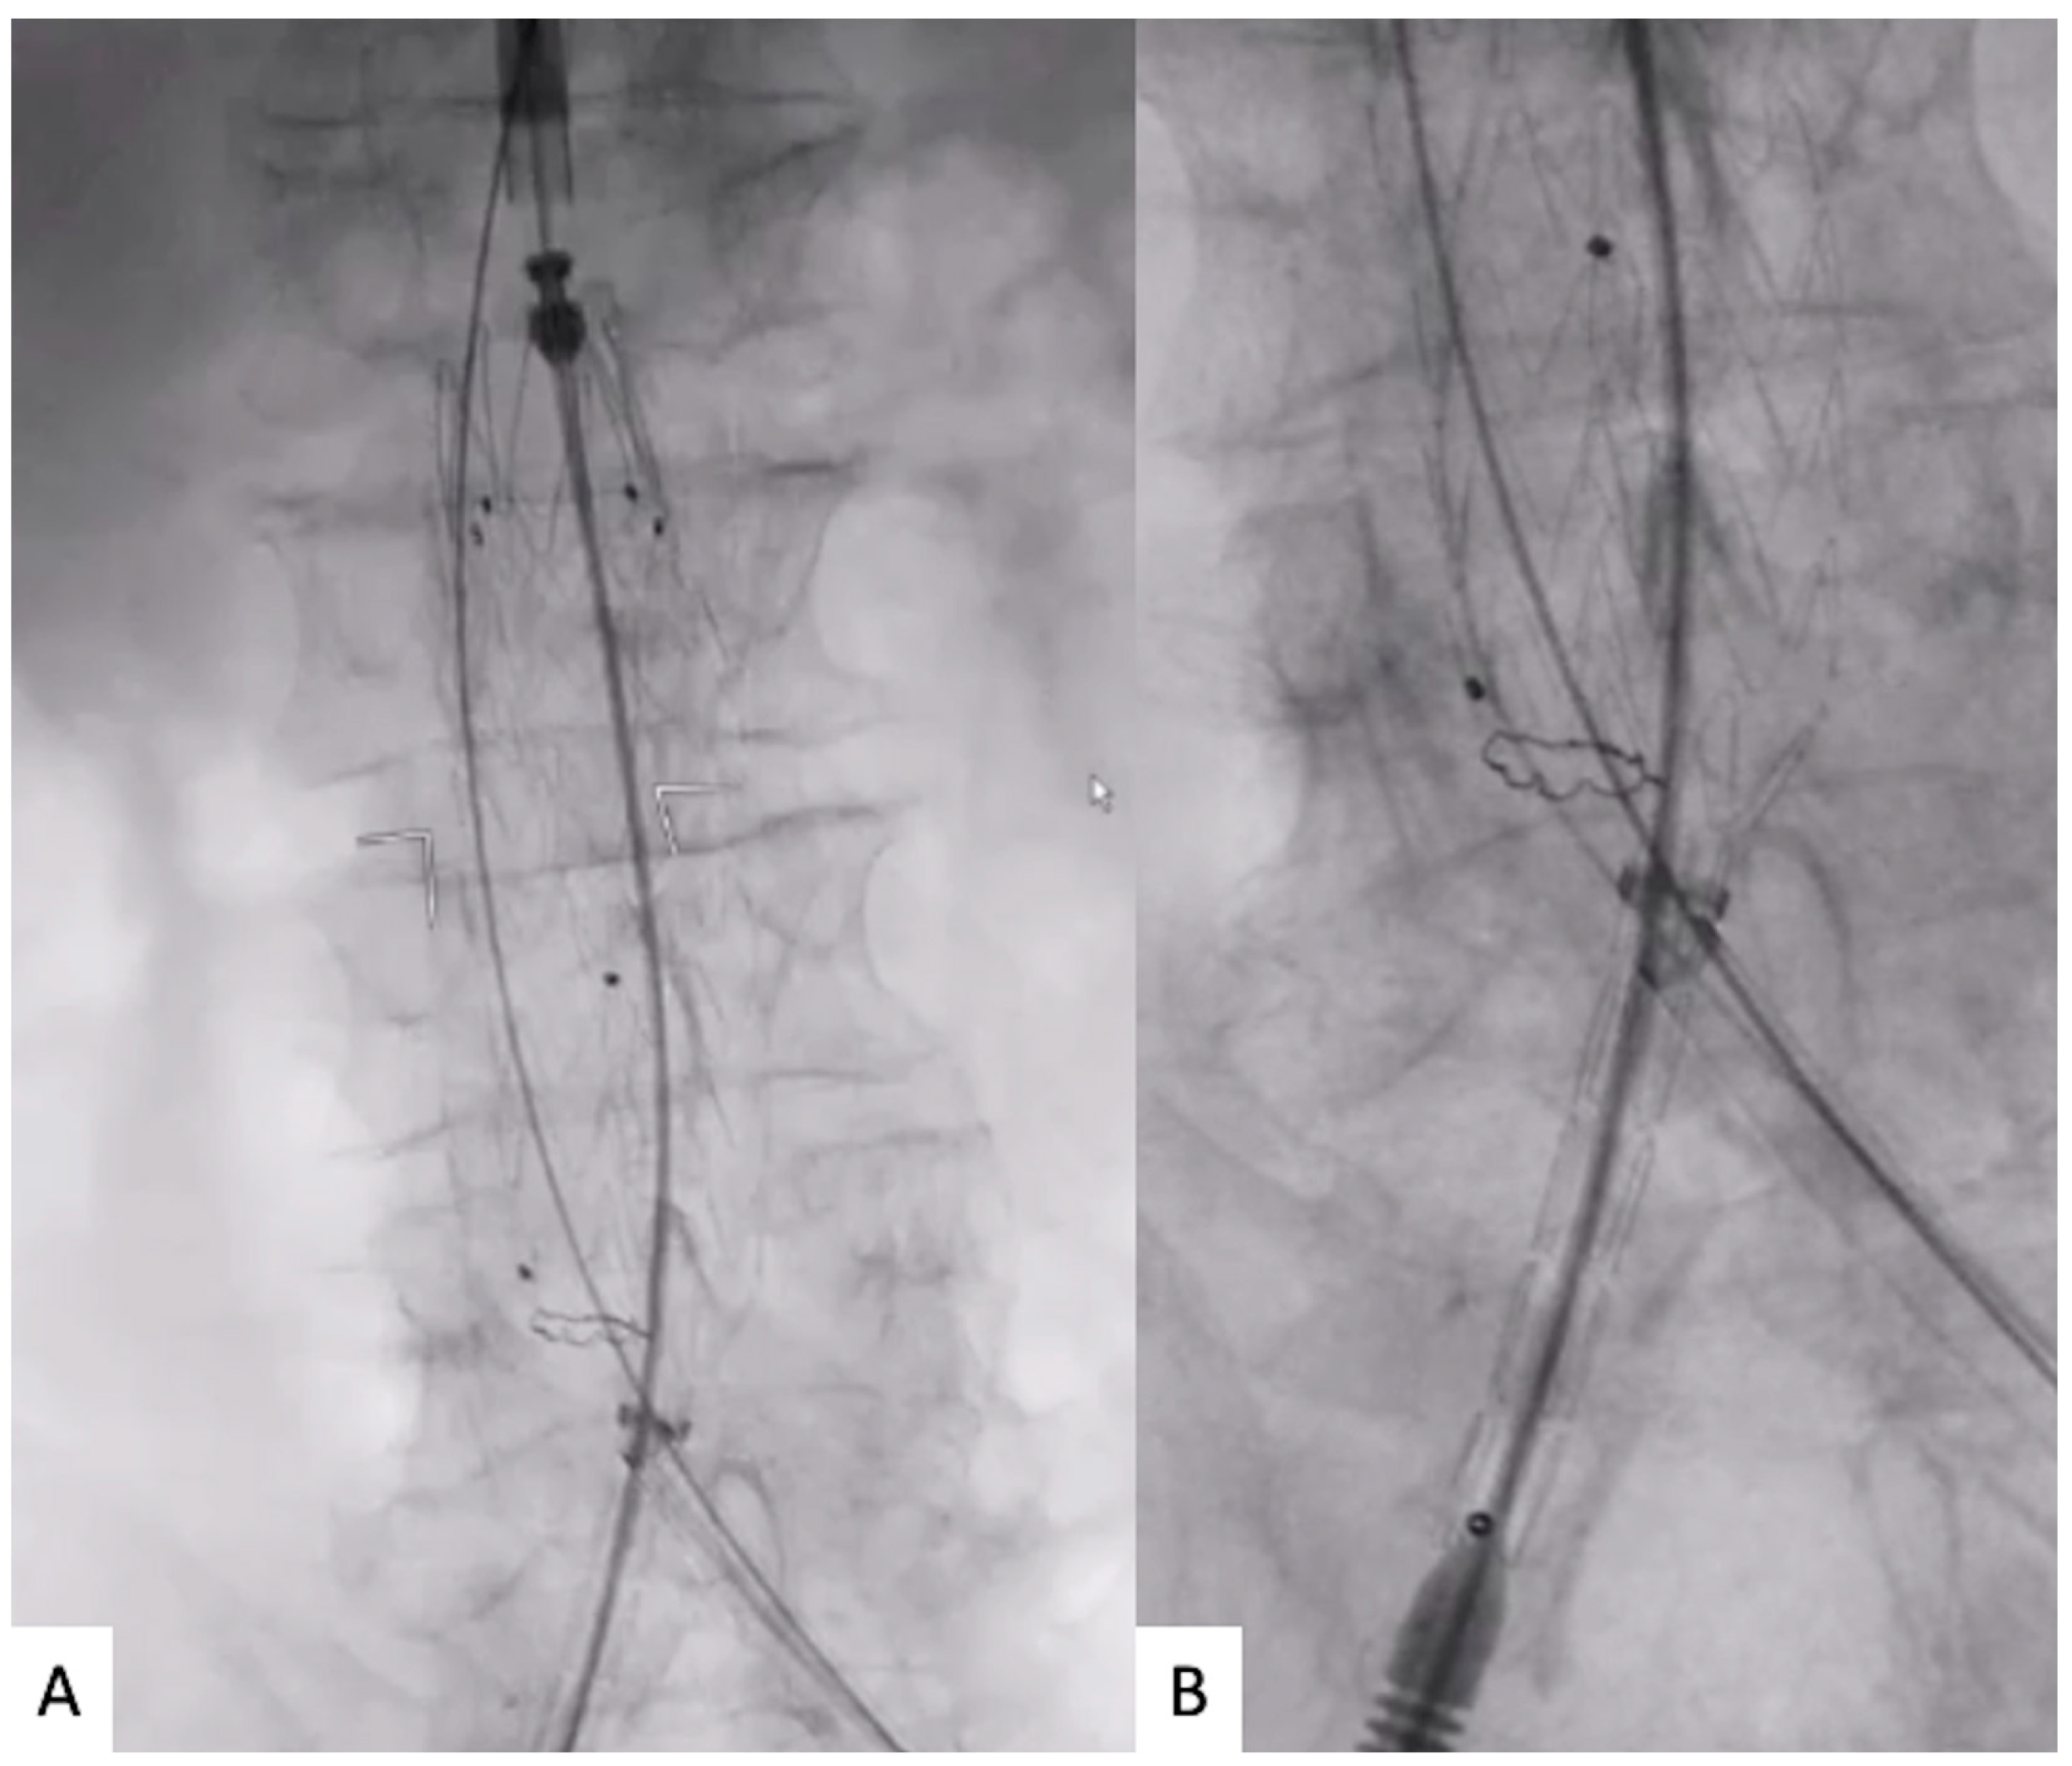

Through the main access, the main body was advanced and positioned at the level of the renal arteries. At this point, the positioned main body was rotated to orientate the distal markers of the contralateral gate in the direction of the route of the contralateral wires. The aim of the orientation is to allow the contralateral gate to open as close as possible to the contralateral wireless route (Figure 2).

Figure 2.

(A) Main body introduction before orientation towards the contralateral supported sheath route. (B) Main body rotation to orientate the distal markers of the contralateral gate in the direction of the route of the contralateral wires.